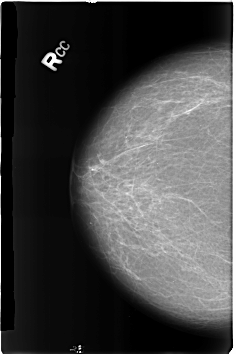

Volume: benign_without_callback_01 Case: B-3185-1

B_3185_1.RIGHT_CC

RIGHT_CC LINES 4592 PIXELS_PER_LINE 3056 BITS_PER_PIXEL 12 RESOLUTION 50 NON_OVERLAY